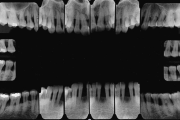

Krooniline parodontiit

Krooniline parodontiit on mikroobide poolt põhjustatud hammaste tugikudede põletik, mille tulemusena tekib progresseeruv alveolaarluu (nähtav röntgenograamil) ja periodontaalligamendi destruktsioon, igemetaskute moodustumine, igeme retsessioon või mõlemad kahjustused kombineeritult. Loe edasi »

- luu destruktsioon (5)

- vertikaalne luukadu (2)

- horisontaalne luukadu (3)

- hamba kinnitussidemete kadu (3)